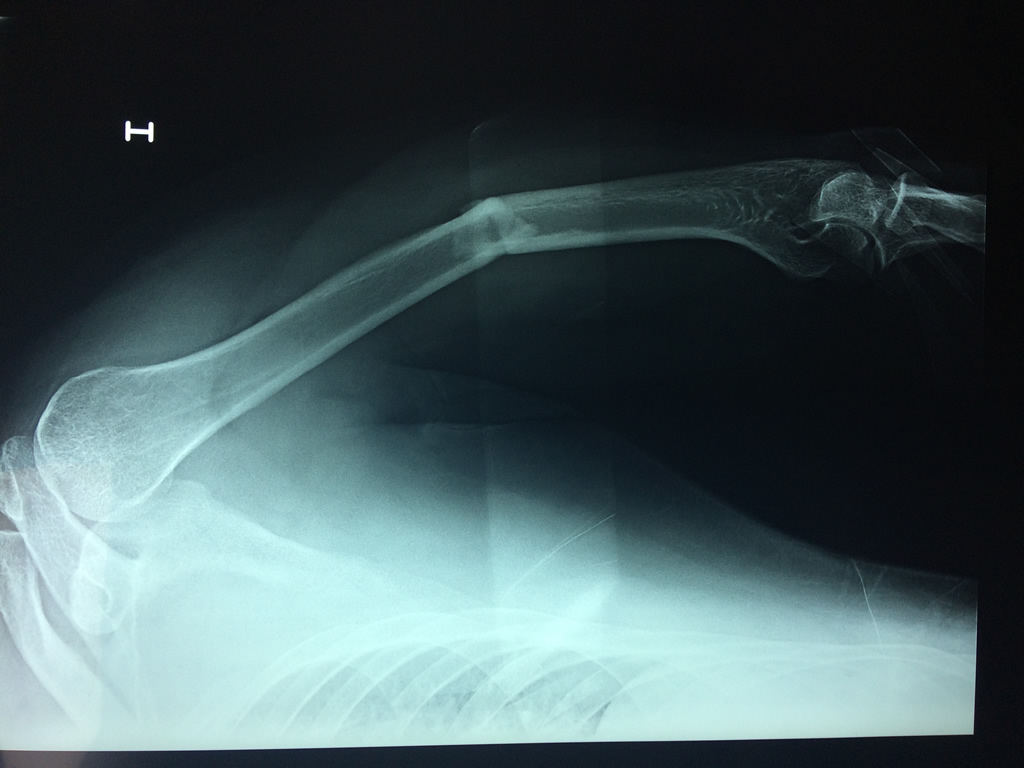

Cirugías de Codos - Húmero

El Húmero (en latín, humerus) es el hueso más largo de las extremidades superiores en el ser humano. Forma parte del esqueleto apendicular superior y está ubicado en la región del brazo. ... El extremo proximal del húmero tiene la cabeza, cuellos quirúrgico y anatómico y tubérculos mayor y menor.